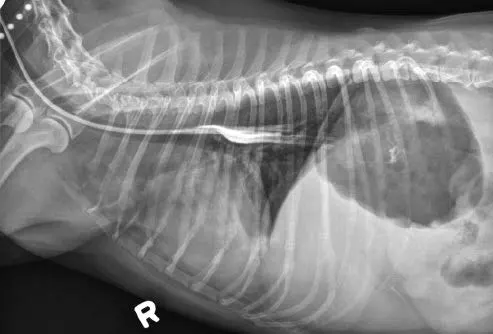

Tubes can be accidentally misplaced in the trachea (Figure 2A), nasopharynx, or nasal cavity, and subsequent feeding may result in aspiration pneumonia; therefore, appropriate placement should be confirmed before feeding is initiated. Various inexpensive methods can help verify tube location: laryngoscopic visualization of the tube entering the esophagus; suction to verify negative pressure; air infusion while auscultating the abdomen for borborygmus; infusion of sterile saline or nonionic contrast medium (Figure 2B), which sometimes elicits a cough with tracheal placement; or pH assessment of fluid aspirated from the tube.

Inadvertent placement of an NG tube in the trachea and bronchus of a miniature dachshund (11 years of age). This dog had a severe pulmonary interstitial pattern secondary to infusion of 20 mL of sterile saline through the tube; it had no cough reflex during infusion (A). After injection of 3 mL of iohexol 240, positive contrast medium outlined the alveoli, particularly in the caudodorsal thorax, confirming tube misplacement (B). The following day, radiography confirmed that contrast medium and saline had been cleared from the lungs.

Verify tube location with survey (A) or contrast (B) radiography. Inject 2–3 mL of iohexol or other nonionic, iodinated contrast medium into the tube, followed by 3–5 mL of air or sterile saline. Note how the contrast medium highlights the esophageal folds.